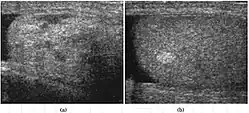

Fig. 27. Varicocele. (a) Multiple tortuous tubular like structure are seen in the left scrotum. (b) Color Doppler sonography shows vascular reflux during Valsalva's maneuver.

Fig. 28. Intratesticular varicocele. (a) Dilated tubular structures are seen within the testis. (b) Presence of vascular reflux is noted during Valsalva's maneuver.

Varicocele refers to abnormal dilatation of the veins of the spermatic cord due to incompetence of valve in the spermatic vein. This results in impaired blood drainage into the spermatic vein when the patient assumes a standing position or during Valsalva's maneuver. Varicoceles are more common on the left side due to the following reasons (a) The left testicular vein is longer; (b) the left testicular vein enters the left renal vein at a right angle; (c) the left testicular artery in some men arches over the left renal vein, thereby compressing it; and (d) the descending colon distended with feces may compress the left testicular vein.

The US appearance of varicocele consists of multiple, hypoechoic, serpiginous, tubular like structures of varying sizes larger than 2 mm in diameter that is usually best visualized superior or lateral to the testis [Fig. 27a]. Color flow and duplex Doppler US optimized for low-flow velocities help confirm the venous flow pattern, with phasic variation and retrograde filling during a Valsalva's maneuver [Fig. 27b]. Intratesticular varicocele may appear as a vague hypoechoic area in the testis or mimics tubular ectasia. With color Doppler, this intratesticular hypoechoic area also showed reflux of vascular flow during Valsalva's maneuver [Fig. 28].